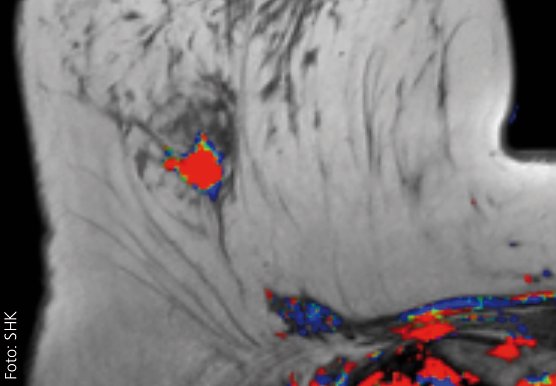

In den vergangenen Jahren hat sich die Palette möglicher Bildgebungen von Tumoren der Brustdrüse deutlich weiterentwickelt. Dies ist insbesondere technischen Innovationen in der Radiologie zu verdanken. Eine frühe Tumordiagnostik ermöglicht bessere therapeutische Optionen und erhöht häufig die Aussicht auf Heilung...

Der Vortrag stellt die aktuellen Möglichkeiten der Bildgebung der Brustdrüse vor und erläutert die innovativen technischen Weiterentwicklungen der jüngsten Zeit sowie die hier verfügbaren Optionen der histologischen Sicherung. Hinzu kommt ein kurzer Einblick in die sogenannte bildgebende Nachsorge, also die radiologische Diagnostik nach behandeltem Mammakarzinom, die wichtig ist, um ein neuerliches Tumorleiden auszuschließen. Es wird auch auf häufig geäußerte Ängste betroffener Frauen eingegangen werden und wie gewohnt Gelegenheit zum gemeinsamen Gespräch geben.